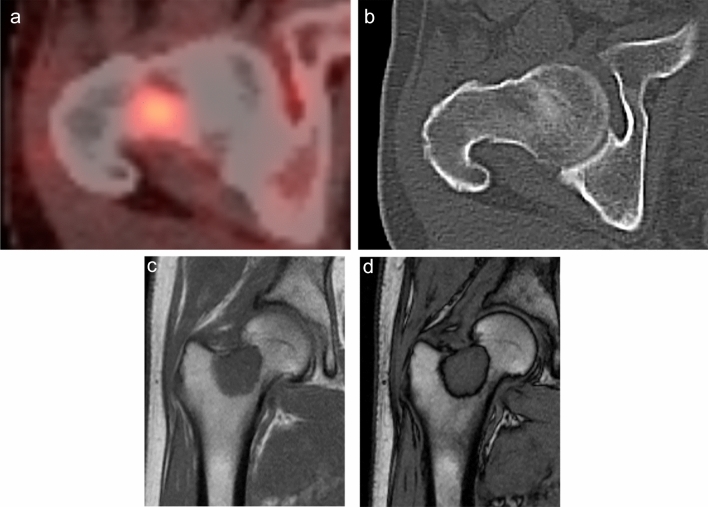

Fig. 2.

A 65-year-old male patient with a history of lung cancer. FDG-PET CT image a shows a focal hot spot in the right femur. CT finding is almost normal but maybe slightly osteoblastic in retrospective interpretation (b). SUVmax of the right femur lesion is 4.8. Coronal in-phase c demonstrates a signal intensity of 100.4 whilst the opposed-phase d shows a signal intensity of 100.3. Signal change ratio (SCR) on CSI was − 0.08%, compatible with a malignant lesion. Histopathological study revealed metastatic lung cancer